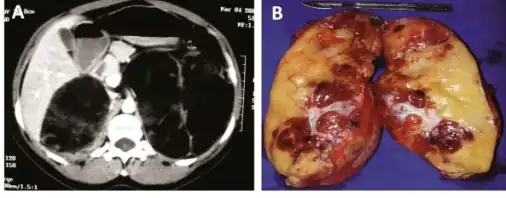

a)CT scan showing heterogeneous bilateral myelolipomas b) macroscopic aspect of left adrenal myelolipomas

Myelolipomas are usually found to occur alone in one adrenal gland, but not both. They can vary widely in size, from as small as a few millimetres to as large as 34 centimeters in diameter. The cut surface has colours varying from yellow to red to mahogany brown, depending on the distribution of fat, blood, and blood-forming cells. The cut surface of larger myelolipomas may contain haemorrhage or infarction.[1]

The cut surface shows colour variegation from yellow to red to brown depending on the distribution of fat, blood and myeloid elements -

Most myelolipomas are unexpected findings on CT scans and MRI scans of the abdomen. They may sometimes be seen on a plain X-ray films.[4]